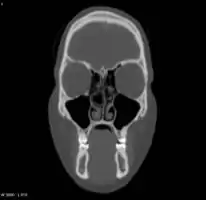

- Right concha bullosa with air fluid level within